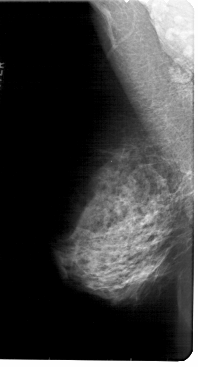

A_1819_1.LEFT_CC

LEFT_CC LINES 5281 PIXELS_PER_LINE 2881 BITS_PER_PIXEL 12 RESOLUTION 43.5 NON_OVERLAY